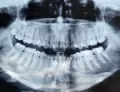

В области шестого зуба выведен материал за верхушку. Как правило, такие зубы дают обострение воспаления и подлежат удалению.